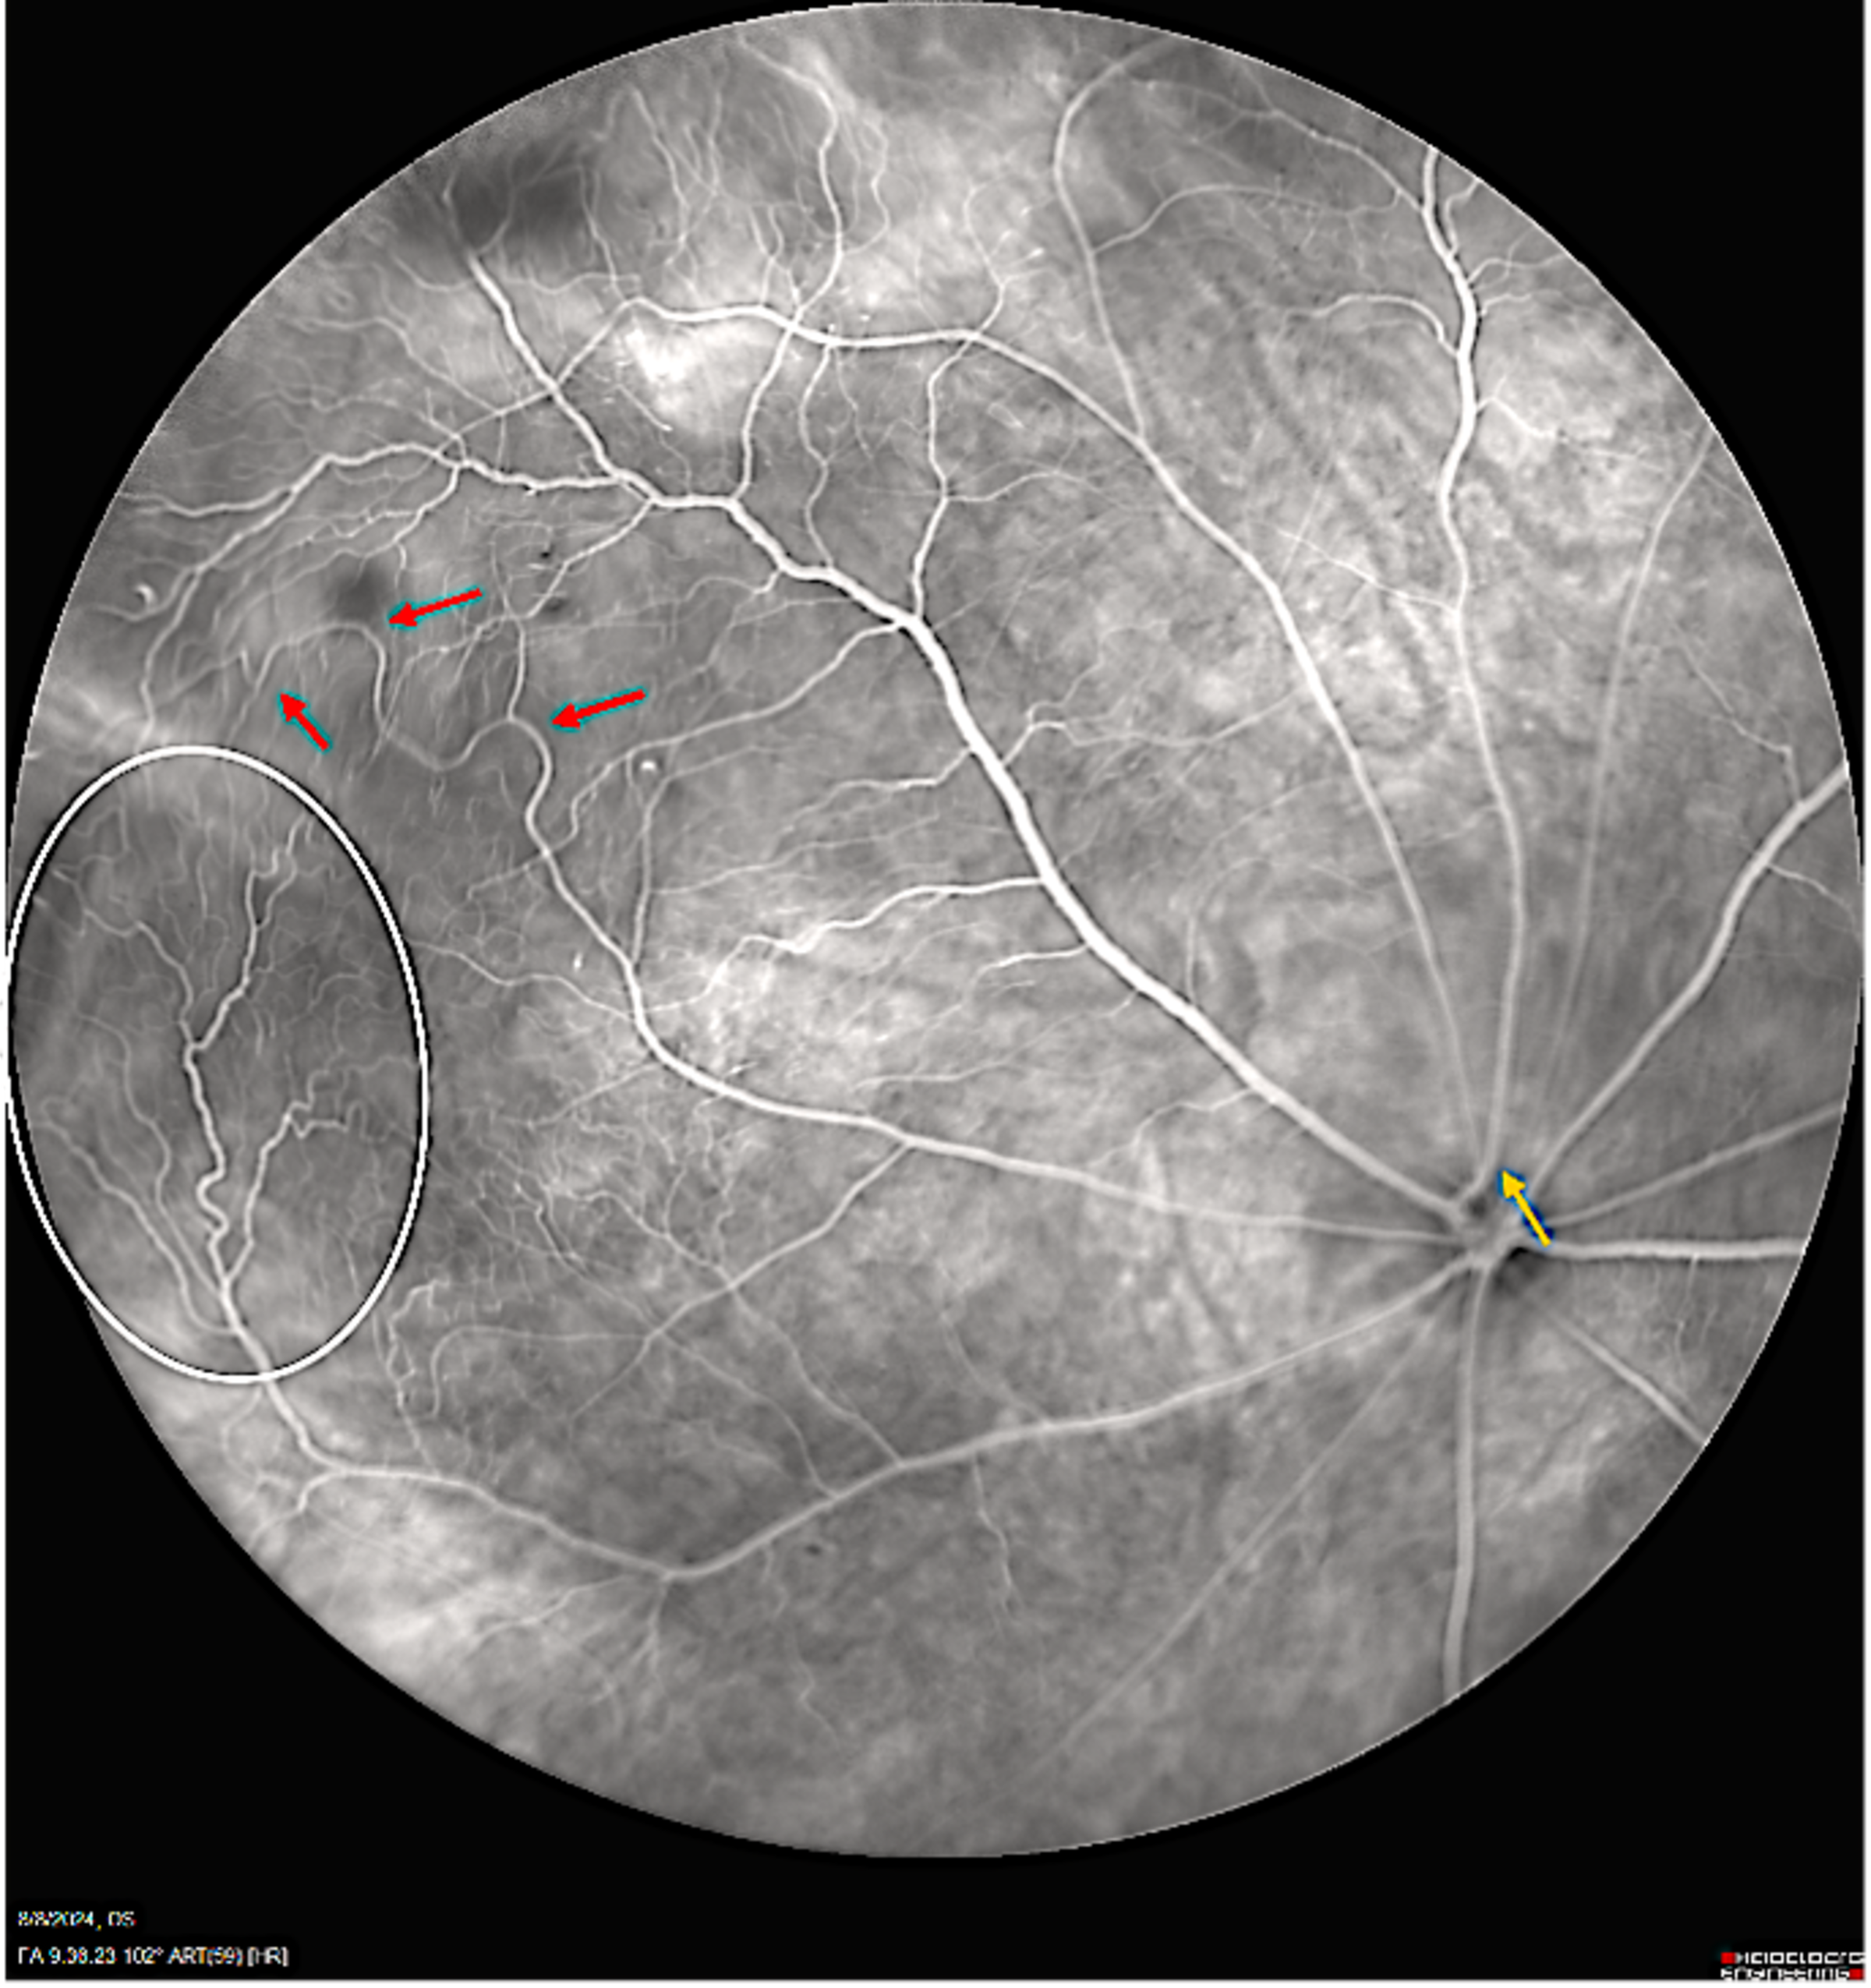

When infants are born prematurely, a host of serious health issues can occur. One of those issues is retinopathy of prematurity (ROP): an eye disorder and loss of vision that can quickly progress.

To build a diagnostic tool, Kang-Mieler and Gan will do something remarkable: create their own expert dataset of what ROP pathology should look like in medical imaging, in order to train an AI how to find it most accurately.

To surmount that challenge, Kang-Mieler and Gan will work with Stevens post-doctoral fellows and graduate and undergraduate student teams to collect animal ROP images and process them, extracting the most useful predictive features from the images, then using them to teach an AI model to generate the best-possible “synthetic” images of human ROP by employing generative AI image-translation techniques.

This new, synthetic image data can then be used to train neural networks that will assist ophthalmologists in spotting ROP or tracking the progression of the disease.

“One strength of our approach is that we have good data on the progression of ROP through the lifetime of animals, from its emergence to development,” adds Kang-Mieler. “That has been captured pretty robustly in the imagery. If we can successfully utilize this information for human health prediction, it could benefit thousands of prematurely born infants.”